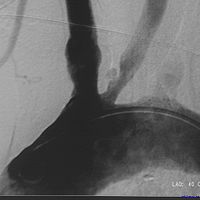

脑血管造影多普勒证实有颅内动脉狭窄者,药物治疗无效时,可考虑手术治疗。